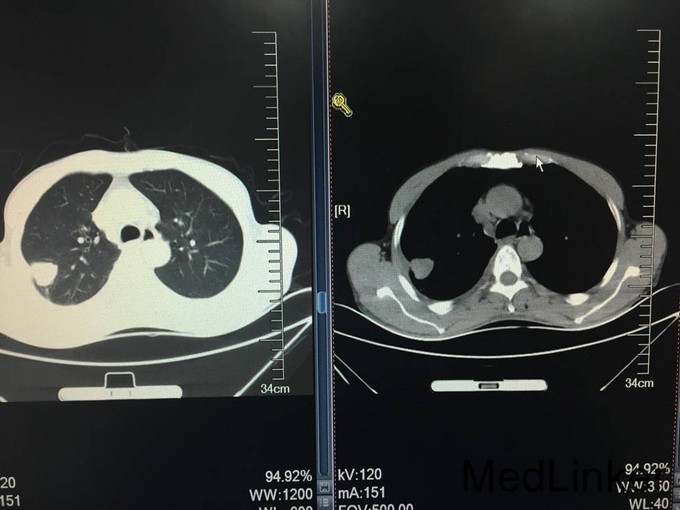

患者老年男性,以“胸闷气短8天”为主诉入院。 患者8天前无明显诱因出现胸闷气短,活动时加重,伴间断咳嗽咳痰,痰为白痰,伴间断发热,体温最高38.8℃,无发冷及寒战,夜间盗汗明显。自行口服阿莫西林、阿奇霉素等药物,症状未见明显缓解,遂就诊于沈阳市第五医院。行肺CT检查,提示:右侧胸腔包裹下积液并左肺下叶膨胀不全,建议进一步检查及复查。左肺上叶陈旧病变。血常规未提示白细胞及中性粒细胞百分比水平升高。患者病来无头晕头痛,无胸痛咯血,无恶心呕吐。食睡眠差,大小便如常,体重未见明显减轻

查体:T:37.5℃,BP:105/80mmHg,P:80次/分,R:18次/分;神清语明,步入病房,查体合作,睑结膜无苍白,口唇无发绀,浅表淋巴结未触及肿大,咽无充血,扁桃体未见肿大,颈软,气管居中,颈静脉无怒张。双肺听诊呼吸音粗,右侧下肺野呼吸音消失,双肺未闻及明显干湿啰音。心界不大,心音钝,节律齐,心率80次/分,各瓣膜听诊区未闻及杂音。全腹软,无压痛,无反跳痛及肌紧张,肝脾肋下未触及,肝肾区无叩痛,无杵状指,双下肢无水肿。 CRP:137.0mg/L。血常规:白细胞计数 6.7*10^9/L,中性粒细胞百分比 70.8%,血红蛋白115g/L,血小板计数 356*10^9/L。降钙素原检测:降钙素原 0.065ng/mL。军团菌、结核抗体、支原体抗体、衣原体抗体均阴性。凝血五项:凝血酶原时间 13.80秒,纤维蛋白原含量 5.84g/L,D-dimer 1101ug/L。一般细菌涂片检查:细菌涂片结果。呼吸道正常菌群。1-3-β-D葡聚糖定量检测:132.8。甲功系列、肺癌系列无异常。生化:总蛋白 54.1g/L,白蛋白 32.5g/L,前白蛋白 0.07g/L,血糖5.01mmol/L,痰结核培养均阴性,患者未成功留取痰结核菌涂片化验。患者入院第二日请介入科会诊,行右侧胸腔穿刺引流术,留置右侧胸腔引流管一枚,引流淡黄色透明液体,引流第一天引流液体800ml,将引流管夹闭,引流液留取化验。胸水化验回报:LDH:乳酸脱氢酶 583;胸腹水常规检查:李凡他试验 阳性(+);白细胞计数 2.89210^9/L;单个核细胞百分比 96.2%;体液ADA:腺苷脱氨酶 61U/L;细菌培养:培养结果 未见细菌生长。胸水结核菌涂片及结核菌培养均阴性。血T-SPOT:混合淋巴细胞培养 50细胞数;A抗原刺激+γ-干扰素 11SFCs/2.5*105PBMC;B抗原刺激+γ-干扰素 6SFCs/2.5*105PBMC。患者胸水病理检查未查见肿瘤细胞。目前患者化验结果提示胸水ADA水平较高,胸水李凡他试验阳性,胸水淋巴细胞比例较高,考虑患者结核性胸水可能性大。患者近日流量管未见引流液流出,复查肺CT,结果:右肺上叶结节,性质待定。右侧胸腔积液,叶间包裹性积液,右肺下叶部分受压不张。左肺上叶钙化灶,双肺散在慢性炎症。心包积液。右侧心膈角淋巴结稍增大。左肾低密度影,必要时进一步检查。请胸科医院会诊,考虑患者结核胸膜炎可能性大,建议转入胸科医院行诊断性抗结核治疗,同时反复胸水病理检查除外恶性。